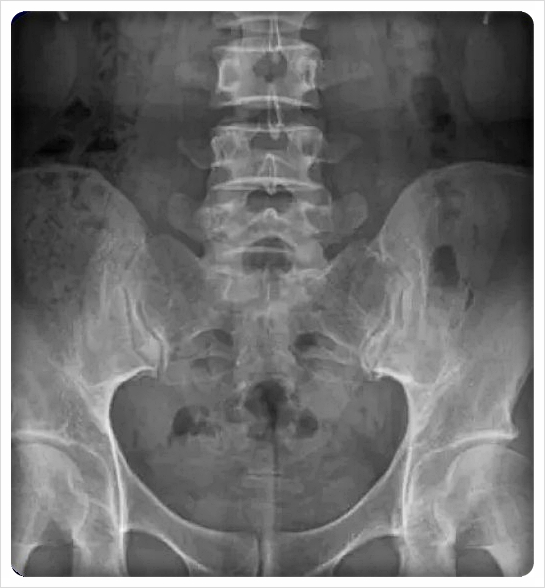

전방 경사는 골반 앞쪽이 아래로 내려가고 뒤쪽이 올라간 형태, 후방 경사는 그 반대로 뒤쪽이 내려간 상태를 말합니다.

오래 앉아 있는 습관, 엉덩이 근육 약화, 허리 과사용과 밀접한 관련이 있습니다.

많은 분들이 경험하지만, 스스로는 잘 알아채지 못하는 경우가 많습니다.

허리가 자주 뻣뻣하거나 엉덩이가 쉽게 뭉친다면 이미 전후방 경사가 어느 정도 진행된 상태일 수 있습니다.